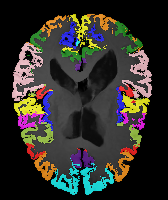

Image Manual Seg DA-1 Mono-21 DA-21 Mono-65 Refer to caption Refer to caption Refer to caption Refer to caption Refer to caption Refer to caption

Figure 2:  Examples of knee MRI registration (top) and brain MRI segmentation (bottom) results. Top: The first two columns are the moving image/segmentation and the target image/segmentation followed by the warped moving images (with deformation grids)/segmentations by different models. Bottom left to right: original image, manual segmentation, and predictions of various models. Mono-i𝑖i and DA-i𝑖i represent the mono- and DA models with i𝑖i manual segmentations respectively.

Image Manual Seg DA-1 Mono-5 DA-5 Mono-200 Refer to caption Refer to caption Refer to caption Refer to caption Refer to caption Refer to caption

Figure 4: Examples of brain MRI registration (top) and knee MRI segmentation (bottom) results. Top: The first two columns are the moving image/segmentation and the target image/segmentation followed by the warped moving images/segmentations by different models. Bottom left to right: original image, manual segmentation, and predictions of various models. Mono-i𝑖i and DA-i𝑖i represent the mono- and DA models trained with i𝑖i manual segmentations respectively.